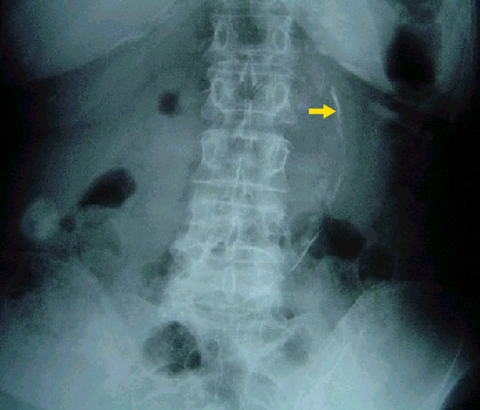

What is the arrow pointing to?

Calcified aortic aneurysm. Calcification in the wall of the abdominal aortia is a common finding in atherosclerosis, especially if you also have DM. The aorta in this pt is enlarged and demonstrates RIMLIKE calcification (calcification that has occurred in the wall of a hollow viscus). An aneurysm is present when the diameter of the abdominal aorta exceeds its normal diameter by >50%.